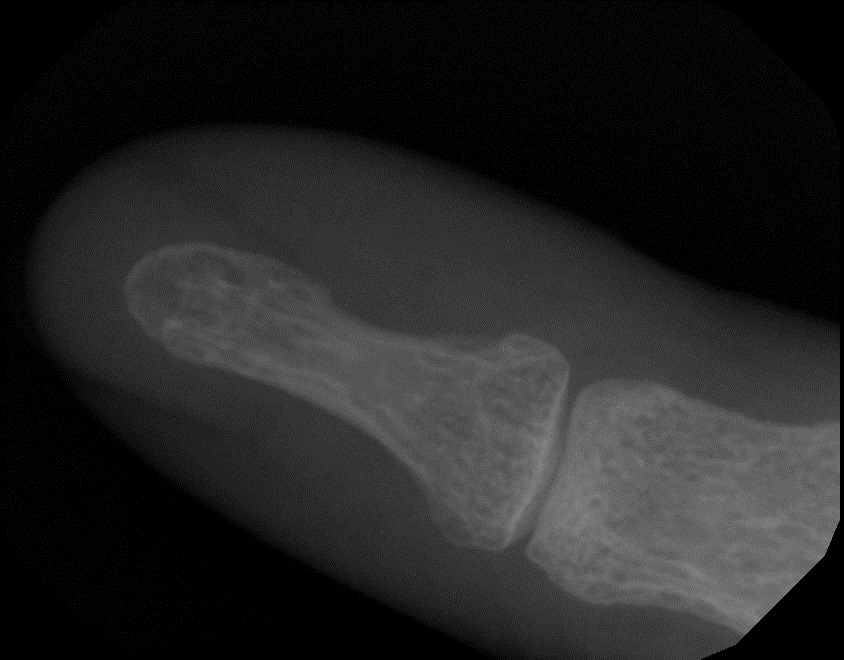

쿨죠님의 아이디어에 영감을 얻어, 출근 길에 꽃 하나를 따, 제가 가진 가장 비싼 센서 앞에 놓고 셔터를 조심스레 눌렀습니다. 셔터 스피드는 물론 가장 빠른... 0.01 초. 아무 것도 나오지 않더군요. 쿨럭 -_-;;; 그래서 제 새끼 손가락과 휴대폰 카메라를 엑스레이로 찍어 올려봅니다.

새끼 손가락